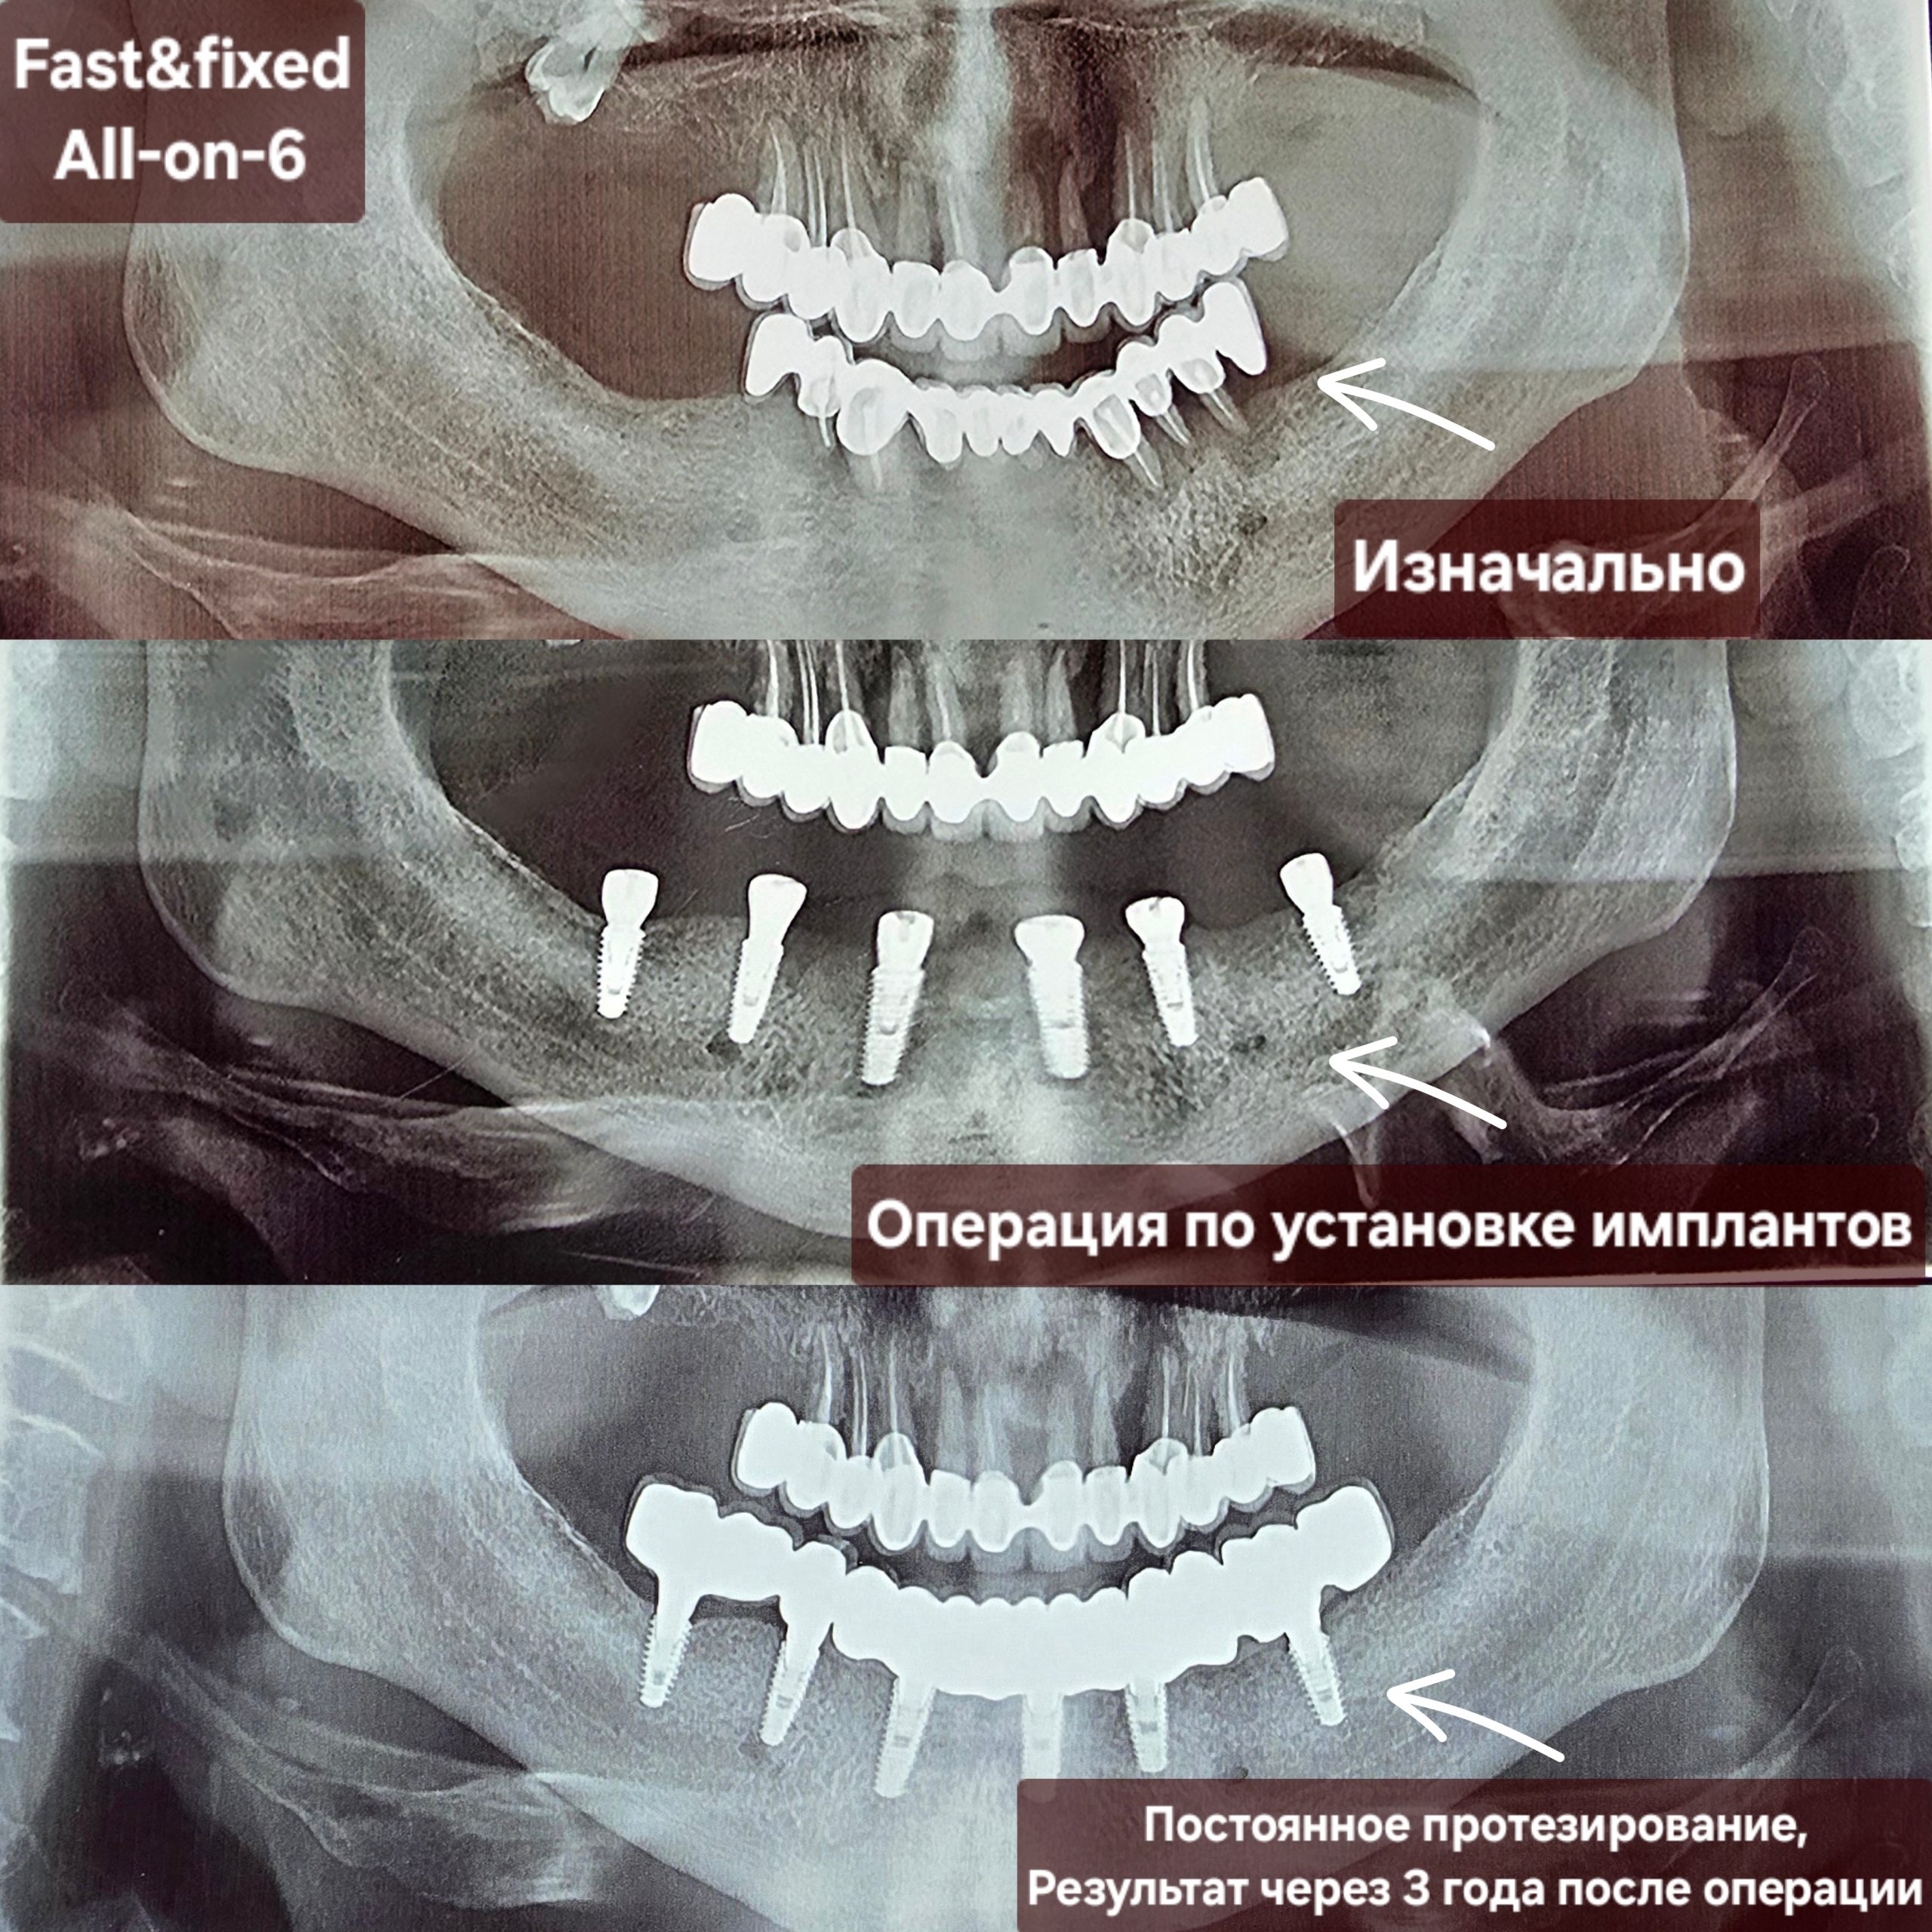

Период заживления

Фаза заживления и интеграции имеет решающее значение для успеха лечения с помощью системы All-on-X. После установки имплантатов обычно требуется период заживления в несколько месяцев (минимум 6 месяцев) для их интеграции в окружающую костную ткань, этот процесс известен как остеоинтеграция.

Окончательная фиксация постоянного протеза.

После того как зубные имплантаты полностью срастутся с челюстной костью, стоматолог заменит временный протез постоянным. Это несъемный мостовидный протез из металло-керамики или циркониево-керамического материала, имитирующий внешний вид и функцию естественных зубов, чтобы пациент мог наслаждаться своей новой улыбкой.